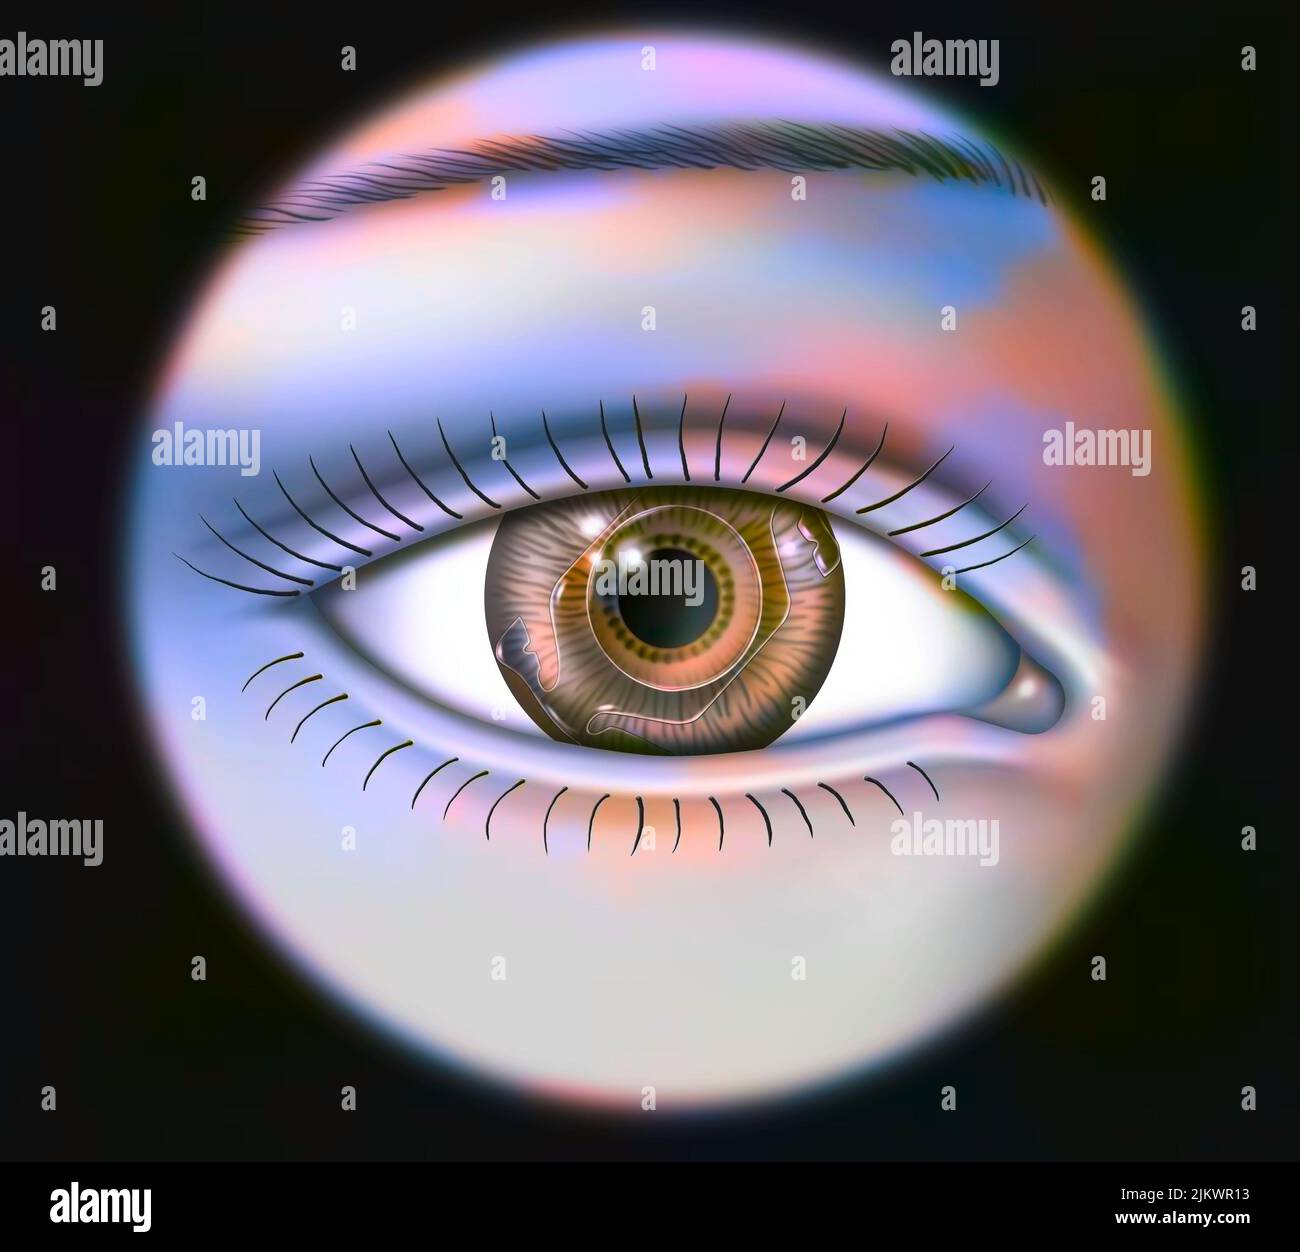

RF2JKWT9A–Oeil, cataracte, phacoémulsification - étape 2: Consiste à casser la lentille avec une sonde.